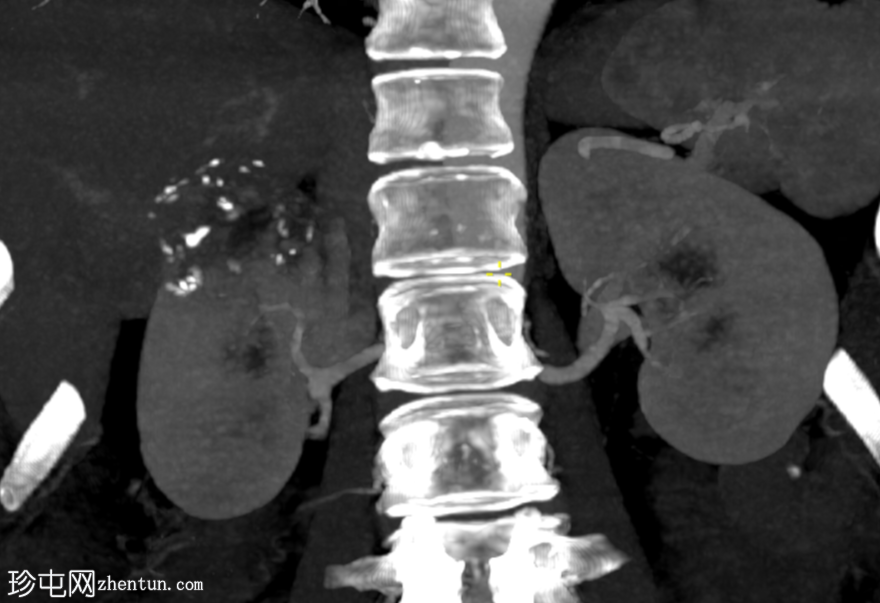

冠状位增强扫描

门静脉期

右肾上极前外侧可见一边界清晰、分叶状、部分外生性病变,大小约4.0 x 6.8 cm(轴位)。病变内侧为无强化囊性成分,直径2.3 cm(动脉期和门静脉期平均密度均为13 HU);外侧为强化实性成分,直径4.5 cm(动脉期和门静脉期平均密度分别为68 HU和78 HU)。病灶内可见多处小钙化灶。病灶毗邻肝右叶,但未见侵犯肝实质的证据。肾静脉和下腔静脉通畅。肾门水平可见数个小的主动脉腔静脉淋巴结和腔静脉后淋巴结,其中最大的腔静脉后淋巴结短轴直径为7毫米。

右肾中极前缘可见10毫米Bosniak II型囊肿,双侧肾盂旁可见囊肿。右肾下极可见两处肾皮质缺损。肝脏第8段可见5毫米囊肿。未见远处转移。L2椎体可见血管瘤。

右肾部分切除标本的组织病理学检查显示为嫌色细胞肾细胞癌(ChRCC)。